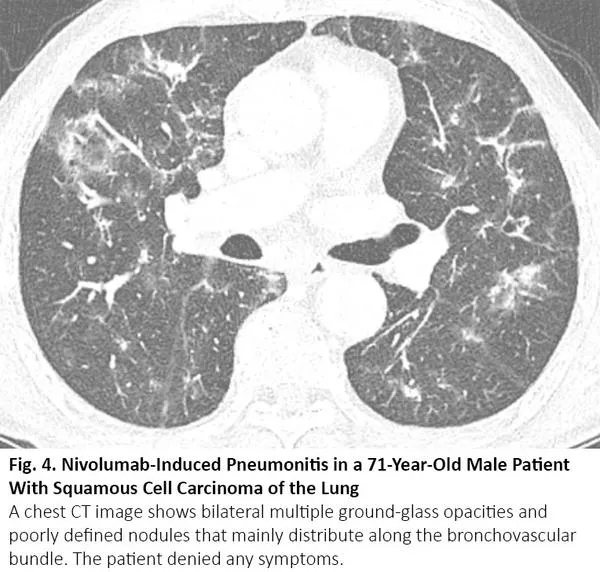

放疗结束后4~12周内可能发生放射性肺炎,有时更晚15。因为放射性肺炎通常发生在照射野,发生于局部,因此在大多数情况下,放射性肺炎与COVID-19肺炎的影像鉴别很简单。然而,当肺炎呈弥漫性分布时,可能无法将放射性肺炎与COVID-19肺炎区分(图5)。

图5. 一位77岁肺腺癌女性患者出现放射性肺炎